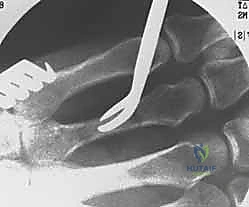

1. التثبيت باستخدام الأسلاك الدقيقة (K-wires)

تُعد هذه الطريقة (Percutaneous Pinning) من التقنيات طفيفة التوغل. يتم إدخال أسلاك معدنية رفيعة جداً عبر الجلد لتثبيت العظم المكسور تحت توجيه الأشعة السينية المستمرة (C-arm) داخل غرفة العمليات.

* الميزة: جروح صغيرة جداً، تعافٍ أسرع للأنسجة الرخوة.

* الإزالة: غالباً ما يتم إزالتها في العيادة بعد 4-6 أسابيع بدون الحاجة لتخدير كامل.

خطوات التثبيت الجراحي - توثيق بصري (Intraoperative Imaging)

يحرص الدكتور هطيف على توثيق خطوات العمل الجراحي لضمان أعلى مستويات الدقة. نستعرض هنا مجموعة من الصور من داخل غرفة العمليات توضح مدى تعقيد ودقة هذه الجراحات:

تتطلب الجراحة انتباهاً خاصاً للأوتار الباسطة والقابضة والأعصاب الدقيقة المحيطة بالعظام. استخدام تقنيات الجراحة الميكروسكوبية (Microsurgery) يضمن عدم الإضرار بهذه الأنسجة الحساسة.